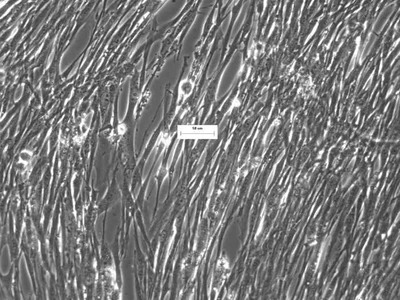

UC-MSCs have cellular functional advantages in migration, proliferation, yield, secretion properties and viability.

Our stem cell products and technology are based upon MSCs. We offer basic tools to support stem cell research and clinical studies of MSCs. Our products include both native MSCs and various derivatives, our MSC-Gro™ specialty cell culture media for support of growth and differentiation of MSCs. Our cell lines include native mesenchymal stem cells, Cancer-Associated Fibroblasts (CAFs) & native fibroblasts for advanced cancer research.

We have developed several novel cell culture media formulations through over 25 years of stem cell research. We now offer various formulations for both stem cells and primary cell culture that feature numerous competitive advantages. These include faster growth, resulting in significantly greater cellular yield, higher quality and potency, vastly improved stability and complete formulations without the necessity of mixing prior to use.